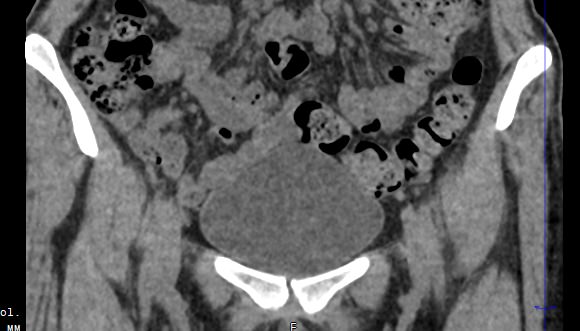

Мультиспиральная КТ мочевого пузыря является частью протокола обследования органов малого таза. Это высокоинформативный рентгенологический метод исследования, позволяющий детально визуализировать мочевой пузырь, нижнюю часть мочеточников, внутренние половые органы, прямую кишку.

Зачастую подобное исследование проводится при мочекаменной болезни (МКБ) для выявления конкрементов, определения их положения, размеров и плотности. Локализация конкремента существенно влияет на терапевтическое лечение МКБ, а наличие дивертикулов стенки мочевого пузыря на возможность самостоятельного выхода камня.

Также при данном исследовании возможно выявить утолщение стенки мочевого пузыря, что при диффузных изменениях может соответствовать проявлениям цистита, а локальные или неравномерные утолщения – характеризовать патологический процесс обусловленный новообразованиями.

Что позволяет увидеть КТ мочевого пузыря

- цистит;

- дивертикулы мочевого пузыря

- цистоцеле

- уретероцеле

- варианты строения мочеточников

- камни мочевого пузыря;

- травмы, разрывы и растяжения органа;

- опухолевые новообразования.